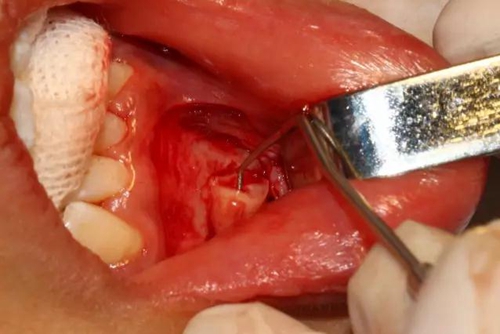

三彎探針取出牙根部分

去除含牙囊壁

創(chuàng)口處理